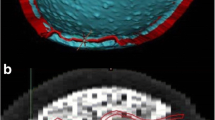

Entire fresh parietal specimens were observed to be comprised of a three-layered structure: external layers consisting of compact, high-density cortical bone and the central layer consisting of low-density, irregularly porous bone structure. Mean thickness of three-layered structure was 6.25 ± 1.46 mm. Mean Young’s modulus and tensile strength of the specimens were 1.40 ± 1.34 GPa and 44.56 ± 21.94 MPa, respectively where no statistically significant differences among genders were detected (p > 0.05). Mean Young’s modulus and tensile strength of the polylactic acid-based three-dimensional implants mimicking geometry of the bone specimens were 1.8 ± 0.7 GPa and 72.8 ± 2.5 MPa, respectively.